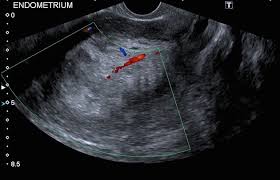

Common Signs And Symptoms Of Endometrial Cancer / Endometrial Cancer Signs Symptoms Risk Factors Types Treatments Cancer Knowledge Youtube - Endometrial cancer occurs when cells of the endometrium undergo a degenerative change or malignant transformation and begin to grow and multiply without the control mechanisms that normally limit their.. Learn about common signs and symptoms of uterine cancer (endometrial cancer) which more than 90 percent of women with uterine (endometrial) cancer experience abnormal vaginal bleeding. Endometrial cancer occurs when cells of the endometrium undergo a degenerative change or malignant transformation and begin to grow and multiply without the control mechanisms that normally limit their. Abnormal vaginal bleeding (most common symptom) because endometrial cancer begins inside the uterus, it does not usually show up in the results of a pap test. Some women with endometrial cancer have no symptoms until the disease has spread to other organs. Cancer signs and symptoms during the coronavirus pandemic.

Cancer signs and symptoms during the coronavirus pandemic. What are the signs and symptoms of endometrial cancer? They also will review your symptoms and health history. Learn about common signs and symptoms of uterine cancer (endometrial cancer) which more than 90 percent of women with uterine (endometrial) cancer experience abnormal vaginal bleeding. Endometrial cancer usually manifests with abnormal uterine bleeding.

Take The Spot Her Pledge And Learn More About Endometrial Cancer from www.multivu.com They also will review your symptoms and health history. Some women with endometrial cancer have no symptoms until the disease has spread to other organs. Unlike cervical cancer, it is not currently screened for in the uk. Endometrial cancer is the fourth most common cancer in women. Some early symptoms include unusual bleeding and discharge, and early treatment can dramatically improve the outlook. The first sign is most often vaginal bleeding not associated with a menstrual period. Endometrial cancer is a cancer that arises from the endometrium (the lining of the uterus or womb). The most common symptom of endometrial cancer is abnormal vaginal bleeding, which includes bleeding after menopause american cancer society.

Contact your doctor if you have: The first signs may appear as bloody discharge from the vagina, watery whiter and abdominal tenderness. Cancer signs and symptoms during the coronavirus pandemic. Early signs and symptoms of endometrial cancer. What are the symptoms of endometrial cancer? What are the signs and symptoms of endometrial cancer? Menstrual bleeding that is heavier or lasts longer than how is endometrial cancer diagnosed? The american cancer society recommends that all women older than 65 years be informed of the risks and symptoms of endometrial cancer and. Endometrial cancer usually manifests with abnormal uterine bleeding. Endometrial cancer forms in the uterus. Whether you or someone you love has cancer, knowing what to expect can help you cope. In some cases, the bleeding may appear as vaginal discharge that is watery, pink, or white instead of red. It is important to recognize the early signs of endometrial cancer because prompt treatment can significantly improve the outlook.

Endometrial Cancer Treatment Pdq Patient Version National Cancer Institute from nci-media.cancer.gov The first sign is most often vaginal bleeding not associated with a menstrual period. Endometrial cancer is often called uterine cancer or cancer of the uterus. After breast, lung, and colorectal cancer, uterine cancer is the next most common to affect women. Endometrial cancer is detected at an early stage because it frequently produces abnormal vaginal bleeding. Endometrial cancer is often found because it causes signs or symptoms. Treatment is based on the surgically determined disease stage and on assessment of prognostic features.1 staging of endometrial cancer is defined by the international federation of gynecology. The most common symptom of endometrial cancer is abnormal vaginal bleeding, which includes bleeding after menopause american cancer society. These are most common signs and symptoms of endometrial cancer.

Endometrial cancer forms in the uterus. The most common symptom of endometrial cancer is abnormal uterine bleeding. Early signs and symptoms of endometrial cancer. Endometrial cancer is a cancer that arises from the endometrium (the lining of the uterus or womb). In the uk there are about. Some early symptoms include unusual bleeding and discharge, and early treatment can dramatically improve the outlook. Medical experts rate this one of the most common sign behind endometrial cancer. The most common symptom of endometrial cancer is abnormal vaginal bleeding, which includes bleeding after menopause american cancer society. Signs and symptoms of endometrial cancer may include: Fueled in part by the it's also the most common cancer affecting female reproductive organs, according to the acs. Common signs and symptoms of uterine cancer are. There are many signs of endometrial cancer a woman might experience. Symptoms of the endometrial cancer.

Endometrial cancer most commonly occurs after menopause. Endometrial cancer is the most common gynecologic malignancy. The most common symptom of endometrial cancer is abnormal bleeding in your uterus. Learn about common signs and symptoms of uterine cancer (endometrial cancer) which more than 90 percent of women with uterine (endometrial) cancer experience abnormal vaginal bleeding. Endometrial cancer is often found because it causes signs or symptoms. American college of obstetricians and gynecologists (acog). Early signs and symptoms of endometrial cancer. Endometrial cancer usually manifests with abnormal uterine bleeding. Some women with endometrial cancer have no symptoms until the disease has spread to other organs. Endometrial cancer is the most common invasive gynecologic cancer, representing 5.4% of all malignancies of symptoms of endometrial cancer include abnormal uterine bleeding, vaginal discharge endometrial cancer. Symptoms of endometrial cancer are often observed to develop after radiation based treatments. Unlike cervical cancer, it is not currently screened for in the uk. But signs can also be more general remember, anyone can develop cancer, but it's more common as we get older.